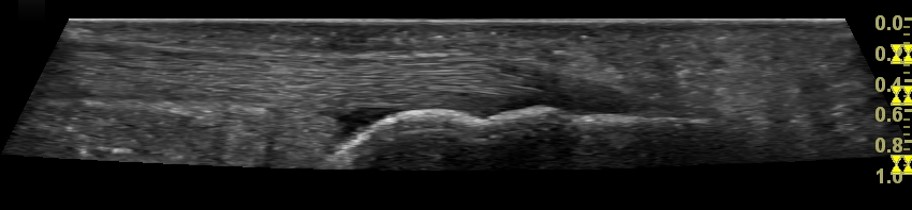

Ultrasound can very clearly show the difference between a normal Achilles tendon (Right top) and one that has tendinopathy (Right Middle) as the tendinopathic tendon is often significantly thicker than a normal Achilles tendon.

In addition to that a tendinopathic tendon tends to be hypoechoic. What that means is that the tendon is less bright on ultrasound. If the tendon has more fluid in it i.e. is more swollen than automatically it appears darker on ultrasound.